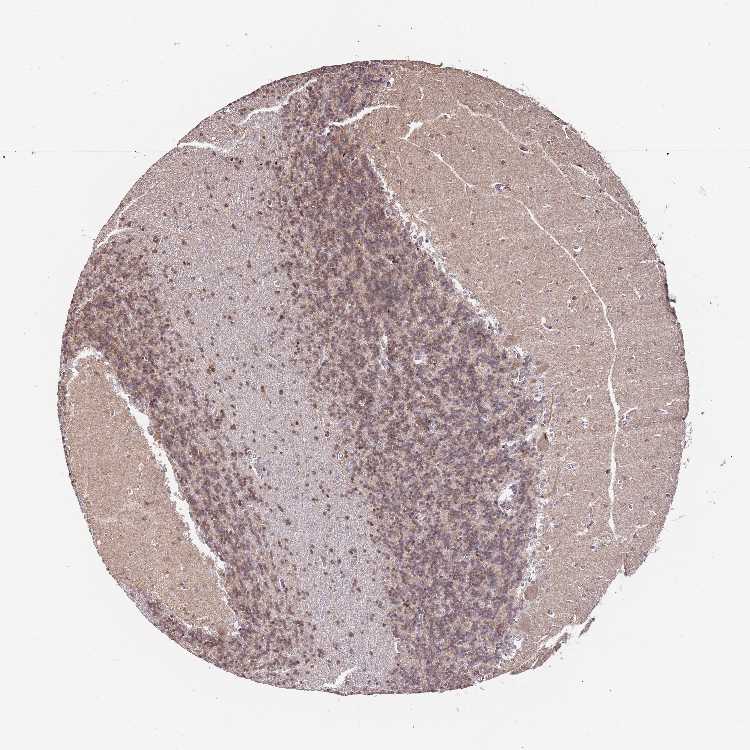

CEREBELLUM - Antibody stainingi

Antibody staining in the annotated cell types in the current human tissue is reported as not detected, low, medium, or high, based on conventional immunohistochemistry profiling in selected tissues. This score is based on the combination of the staining intensity and fraction of stained cells.

Each image is clickable and will lead to virtual microscopy that enables deeper exploration of all samples and also displays staining intensity scores, fraction scores and subcellular localization as well as patient and tissue information for each sample.

Antibody HPA036887Antibody HPA036888

Purkinje cells LowHigh

Cells in granular layer MediumHigh

Cells in molecular layer LowMedium